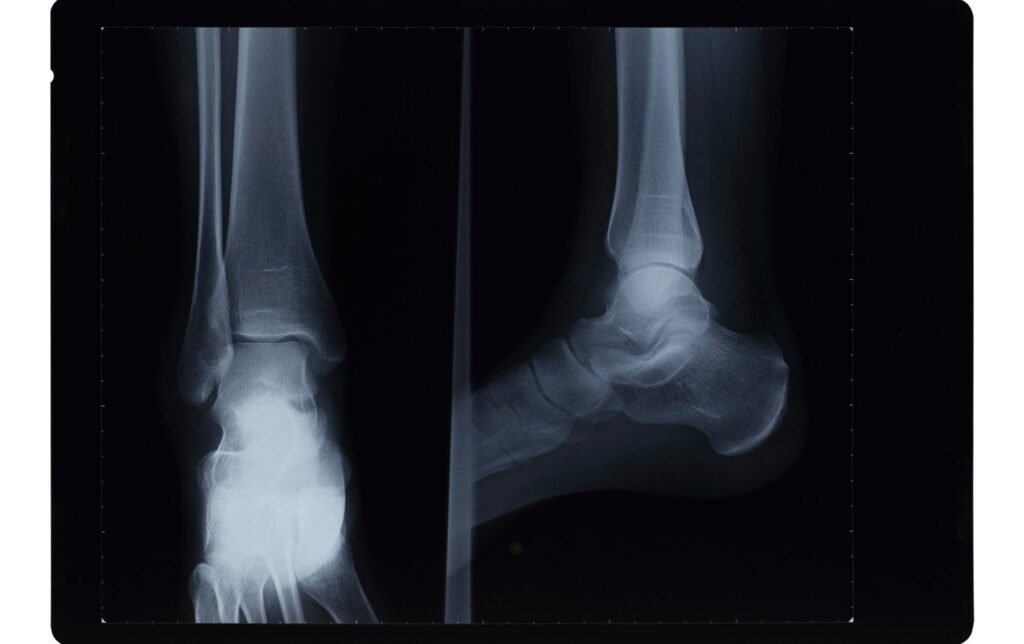

Fracture de stress de la cheville

Les fractures de stress sont de minuscules fissures dans l’os.

Causes

Les fractures de stress sont généralement causées par la surutilisation. Le stress s’accumule avec le temps s’il y a un décalage entre la capacité de notre corps à gérer la charge et le volume/l’intensité de la charge qu’il subit pendant la course.

Symptômes courants

- Douleur qui s’améliore au repos mais s’aggrave à la course. La douleur est souvent localisée dans une zone particulière où se trouve la fracture. La douleur peut être vive.

- Gonflement mineur

- Ecchymoses

- Sensibilité

Traitement

Il est important de se reposer si l’on soupçonne une fracture de stress de la cheville. Si vous continuez à exercer une force sur la zone affectée, la fracture s’aggravera progressivement et vous risquez de vous retrouver avec la cheville dans le plâtre.

La plupart des fractures de stress guérissent avec un traitement non invasif. En fonction de la gravité de la fracture, il faut généralement entre 1 et 3 mois pour qu’une fracture de stress guérisse.